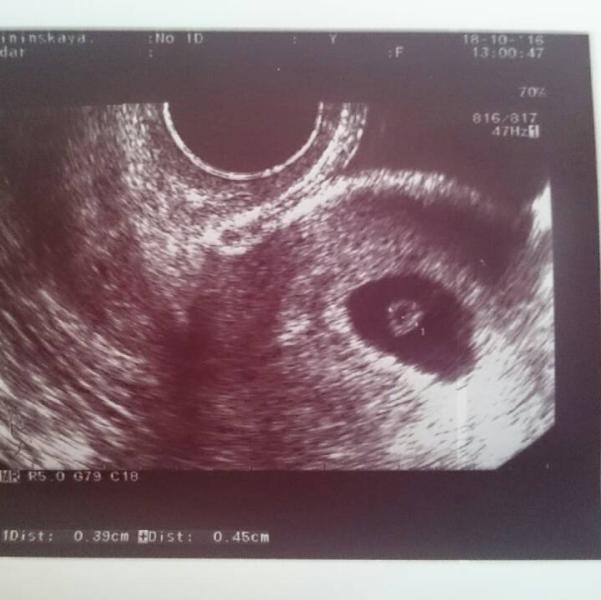

Поехала после гематолога на УЗИ. Ура! Увидели эмбриончик и сердцебиение.)))

Диаметр плодного яйца 22 мм.

Копчико-теменной размер плода 4 мм.

Желточный мешочек 5 мм.

По узи срок написали 5 недель и 3 дня.